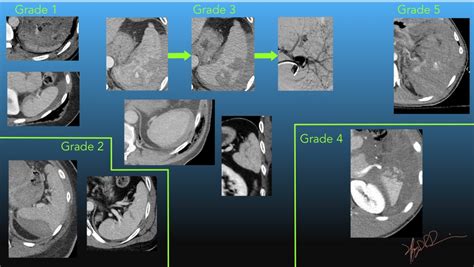

Understand the clinical standards for splenic laceration grading. This guide breaks down the AAST injury scale, covering diagnostic imaging, symptoms, and surgical versus non-operative management strategies. Learn how radiologists and surgeons classify spleen trauma severity to determine the most effective treatment plan for improved patient outcomes in cases of abdominal injury.

TitleAAST Spleen Injury Scale 2018 revision | UW Emergency Radiology